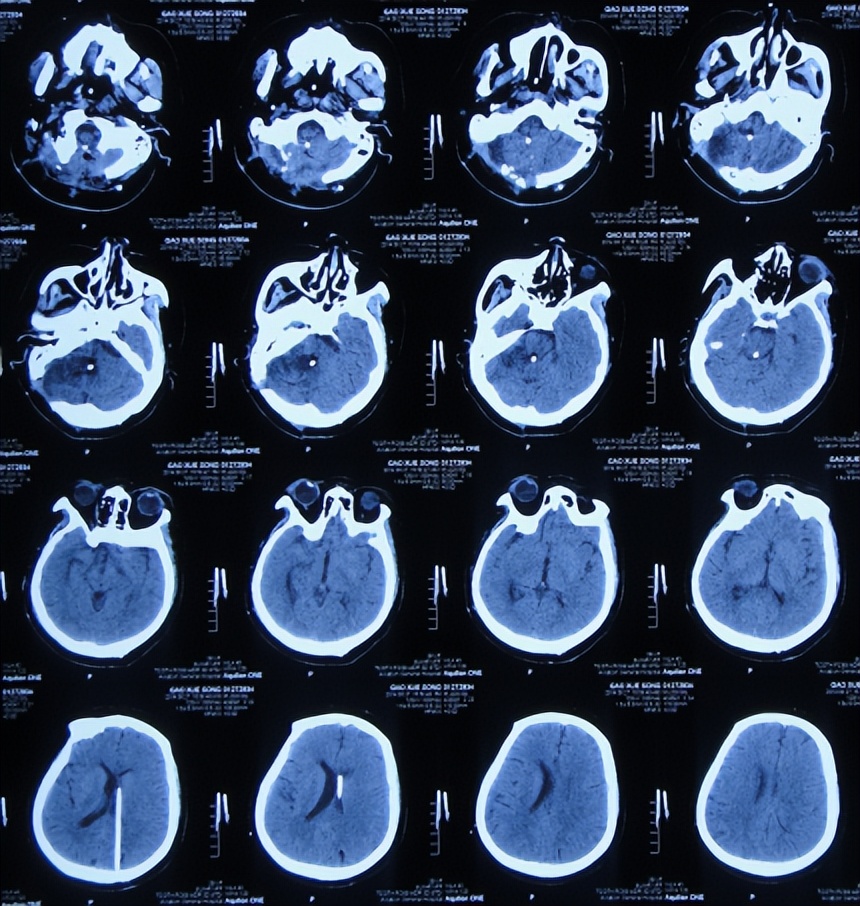

入院时头颅CT示右侧小脑半球低密度影,第四脑室扩张(图-14)。肺片肺部感染(片子丢失);重度贫血,血小板降低,白细胞减少。

图-14:2014年3月20日头颅CT

引流术后8天即2014年4月2日,查头颅CT示四脑室仍有扩张(图-17)。

图-17: 2014年4月2日头颅CT

引流术后20天即2014年4月14日,头颅CT与2014年4月2日比较:右侧小脑半球见片状低密度影;四脑室扩张变小(图-18)。

图-18: 2014年4月14日头颅CT

引流术后41天即2014年5月5日,患者不思进食伴恶心,查头颅CT示四脑室再次扩张变大(图-20)。先观察,如果无改善将行四脑室外引流术。

图-20:2014年5月5日头颅CT

因持续恶心及腹胀不适,2014年5月8日,进行了开颅四脑室腹壁外引流术(图-21)。

图-21:2014年5月8日头颅CT

第四脑室外引流术后15天即2014年5月23日,查头颅CT示四脑室缩小(图-23)。

图-23:2014年5月23日头颅CT

第四脑室外引流术后19天即2014年6月27日,体温正常,但精神差,言语缓慢含糊,查头颅CT示四脑室侧脑室引流管无变化,右侧小脑半球可见片状低密度影;左小脑半球低密度影消失(图-24)。

图-24:2014年6月27日头颅CT